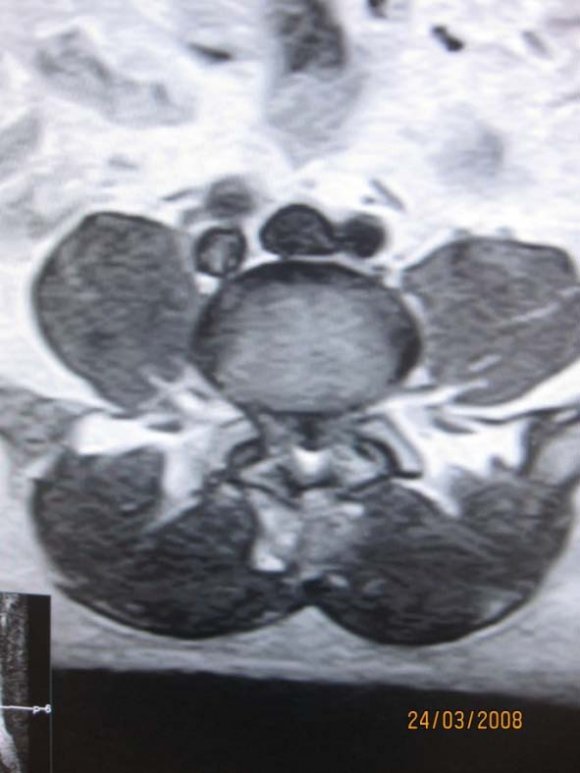

(b) there was no contraindications to MR imaging (e.g. pacemaker, aneurysmal clips, foreign body in globe etc). b) MRI Protocol MR imaging was performed at our hospital, using 0.3 Tesla Hitachi AIRIS 11 MRI machine, and spine phased-array coil. Technical factors used were T1W, T2W, STIR. Sagital acquisitions were used in screening while axial and coronal were used to evaluate the neural foramina. This was followed by T2 STIR images acquired in oblique coronal and sagital planes .Enhanced T1W images with Gadolinium pentate dimeglumine were used in cases of intra-spinal mass lesion or to evaluate herniated disc lesions where T2W images were degraded.

Technical specifications included a slice thickness of 3 and 4 mm for sagittal and axial sequences, respectively; a field of view of 26 and 20 cm for the sagittal and axial images, respectively; and a matrix of 192 by 256. The T 1 -and T 2 weighted axial sequences were stacked slices extending from the inferior aspect of L3 through the inferior aspect of S1.

This pioneer prospective MRI study is paramount because of paucity of such documentations in central African region. Our centre is the second MRI centre in Central African region and the earlier machine in another centre had broken down without any documentations of MRI findings related to LBP. MRI defines the lumbo-sacral spine diagnosis with high specificity allowing the most approximate therapeutic decisions [9]. Back pain is the most frequent cause of limitation of activity among individuals who are less than forty-five years old. [4]. Our largest studied population with low back pain, 31.25% was in the 50-59 age range with male to female ratio of 1:1.14. This is followed by 29% in the 40-49 age range with male to female ratio of 1:0.4. This agreed with high incidence of low back pain in the work force with attendant negative impact on productivity and economy [1].Annually, back symptoms occur in 50% of working age adults in USA [1]. Each year, there are approximately 500,000 Workers' Compensation and personal-injury cases dealing with low-back pain [4]. In this study, detected number of pathologies outweigh the number of studied population. This is because multiple pathologies can exist in one patient . The high signal intensity of the cerebrospinal fluid and epidural fat in T2W sequence makes T2W sequence the most useful in evaluation of discal lesion, which is dorminant pathology as in our study [9]. The commonest pathology in this study is disc hernia with 16 cases (33.3%) with male to female ratio of 3:1. 10 cases (62.5%) of herniated disc occurred at L4/L5 disc level followed by 4 cases (25%) at L5/S1 disc level. At L4/L5 level male to female ratio is 4:1 while equal male to female ratio is seen at L5/S1 level. This predominance of disc herniation at L4/L5 and L5/S1 levels is supported by previous study [12] The reducing gender difference is accounted for by the increasing degeneration, laxity, demineralisation and dessication with ageing in both sexes [9]. This is corroborated by the articular facet degenerative changes seen in almost all cases of disc herniations shown as height reduction and subluxation of the ligamentum flavum of the facet joints [9,12].

Disc herniation can be used to describe a wide spectrum of abnormalities involving disk extension beyond the interspace, from a bulge to a frank extrusion and sequestration; [11]. The terms used to classify disks were defined as follows: normal, no disk extension beyond the interspace; bulge, circumferential symmetric extension of the disk beyond the interspace (around the end plates); protrusion, focal or asymmetric extension of the disk beyond the interspace, with the base against the disk of origin broader than any other dimension of the protrusion; and extrusion, more extreme extension of the disk beyond the interspace, with the base against the disk of origin narrower than the diameter of the extruding material itself or with no connection between the material and the disk of origin [9,11].Sequestered disc are free disc fragment which may migrate below or above the interspace [6]. On MRI examination of the lumbar spine, many people without LBP have disk bulges or protrusions but not extrusions, thus discovery by MRI of bulges or protrusions in people with LBP may frequently be coincidental [11]. There is a hypothesis that the prevalence of extrusions in people with symptoms of LBP may be substantially higher than in people without symptoms [11]. Sequestered or free fragment has high T2 * W signal because their increased water content produces an increase in signal intensity [6]. When it is behind the parent disc, it is round in configuration but oblong on further separation [6]. Annular defects or fissure which can be demonstrated by MRI as decreased signal on the T 2 -weighted image may be a fore-runner to disc hernia and are frequently asymptomatic [11] But any pain , possibly results from leakage of the contents of the nucleus pulposus into the epidural space, with related nerve irritation [11]. The reported prevalence of posterior radial tears at autopsy in asymptomatic people is 40 percent for those between In our study, no distinction was made between disc protusion and extrusion, rather cases where there is protusion of disc anteriorly and behind anterior longitudinal ligament was considered separately and termed disc anteropulsion. 6 cases (12.5%) anteropulsions were seen. Using MRI in 67 people without symptoms, Boden et al. found herniated disks in 20 percent of the people less than 60 years old and in 36 percent of those 60 years of age or older [11]. But our study included symptomatology criterion and discovered 60% of patients 60years and above had disc hernia. Low back ache is one of the most common causes of morbidity in elderly patients and could be due to multiple aetiologies like degenerative-inflammatory lumbar spinal pathology . [2,13] Multiple levels of disc hernia was seen in 56.25% of our patients. MRI examination of 41 women without symptoms showed that 54 percent had a disk bulge or herniation at one or more disk spaces, although only L3-4, L4-5, and L5-1 levels were examined [11]. b) MRI is the preferred investigation for confirming lumbar disc herniation, nerve root entrapment, radiculopathy, and spinal canal stenosis [3]. Lumbar spine stenosis (LSS) is subdivided into relative and absolute LSS according to the anteriorposterior diameter of the spinal canal (physiological value is 22-25 mm) [7]. Relative LSS is when spinal canal measures 10-12 mm in diameter and usually asymptomatic. Whereas absolute LSS (spinal canal <10 mm in diameter) is often symptomatic and is associated with absence of free subarachnoid space [7]. The lateral recess can also be considered in LSS definition (physiological diameter is 3-5 mm) and stenosis is considered if it has a diameter of <2 mm [7]. 32(66.66%) of our studied population had lumbar stenosis. LSS can be mono-segmental or multisegmental, and unilateral or bilateral. Pathoanatomically, stenosis can be classified as central, lateral or foraminal. This is often the sequllae of degenerative disc hernia [7]. Herniated disc is classified into central, centro-lateral and lateral, the commonest is centro-lateral. [6]. Laterally herniated discs and smaller focal disc herniations may be difficult to diagnose with only sagital imaging. Axial imaging will help and has become a routine examination protocol to assess the degree of lateral, neural canal, nerve root and cord involvement [12]. Depending on the extent of the degeneration, central, lateral and foraminal stenosis can occur alone or in combination. The L4-5 spinal discs are most frequently affected by LSS, followed by L3-4, L5-S1, and L1-2 [7].This highest occurrence of lumbar stenosis at L4/L5 is noted in our study with disc hernia the ages of 50 and 60 years and 75 percent for those between 60 and 70 [11]. availability of advanced imaging techniques. [7].

Multiple factors can contribute to the pathogenesis of spinal stenosis, and these can act synergistically to exacerbate the LSS [7].Central stenosis results from degeneration and protusion of the disc, which leads to ventral narrowing of the spinal canal [7]. Foraminal stenosis is a consequence of disc degeneration, with further reduction of the height of the intervertebral space, leading to narrowing of the recess and intervertebral foramina, exerting strain on the facet joints [7]. Such an increase in load leads to facet joint arthrosis, hypertrophy of the joint capsules and the development of expanding joint cysts (lateral stenosis), which in combination propagate spinal instability [7] . Central stenosis is further contributed by the reduced height of the segment and the ligamenta flava forming creases, which exert pressure on the spinal dura from the dorsal side [7]. Concomitant instability due to loosened tendons (for example, the ligamenta flava) further propagates pre-existing hypertrophic changes in the soft tissue and osteophytes, creating the characteristic trefoil-shaped narrowing of the central canal. [7] The clinical features of the condition are heterogeneous, and often, include neurogenic claudication which comprises limping or cramping lumbar pain that radiates into the legs primarily during walking [7]. Degenerative LSS can ultimately lead to the compression of individual nerve roots, the meninges, the intraspinal vessels, and, in exceptional cases, the cauda equine [7] Nerve root compression triggers localized inflammation, which affects the nerve root's excitatory state. [7] In addition, two interdependent vascular mechanisms are hypothesized to assist in the development of neurogenic claudication in LSS: reduced arterial blood flow resulting in ischemia, and venous congestion with compression of the nerves and secondary perfusion deficiency [7].